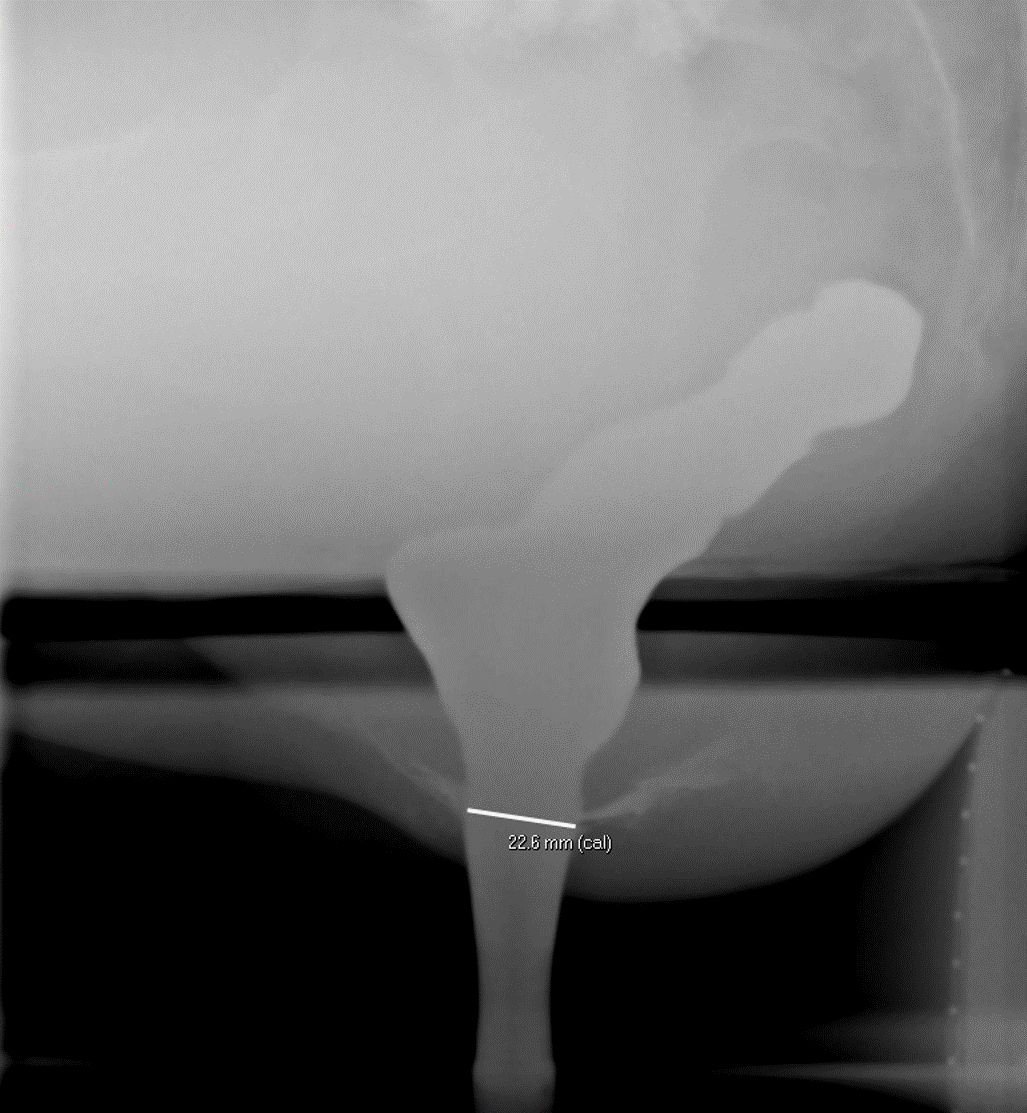

- Measured as the distance between the external anal orifice and the point where the parallel straight sides of the anal canal meet the cone shaped walls of the distal rectum.

- The mean radiographic length of the anal canal is 22mm in men and 16mm in women

(key image 5).